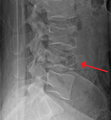

A burst fracture of L4 as seen one plane X ray